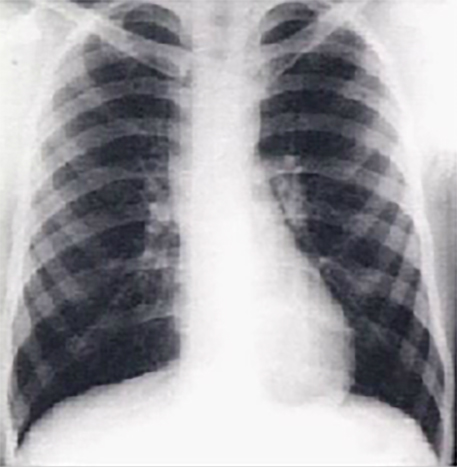

This PA chest X ray shows a dilated ascending aorta.

It demonstrated dilatation of the

ascending portion of the aorta, as evidenced by a prominent bulge in the right mediastinal shadow. Note that the heart size is normal, as reflected by a

cardiothoracic ratio less than fifty percent.